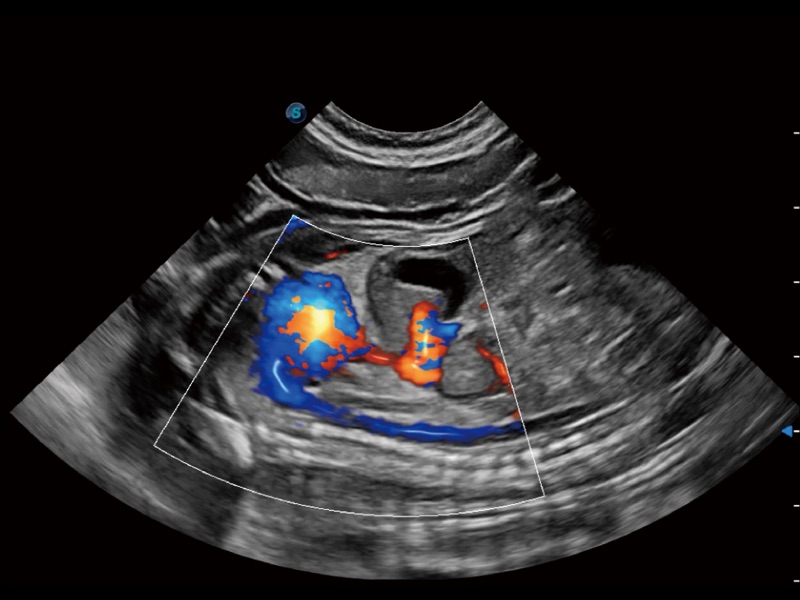

(犬)左室长轴血流

(犬)胎儿主动脉弓立体血流